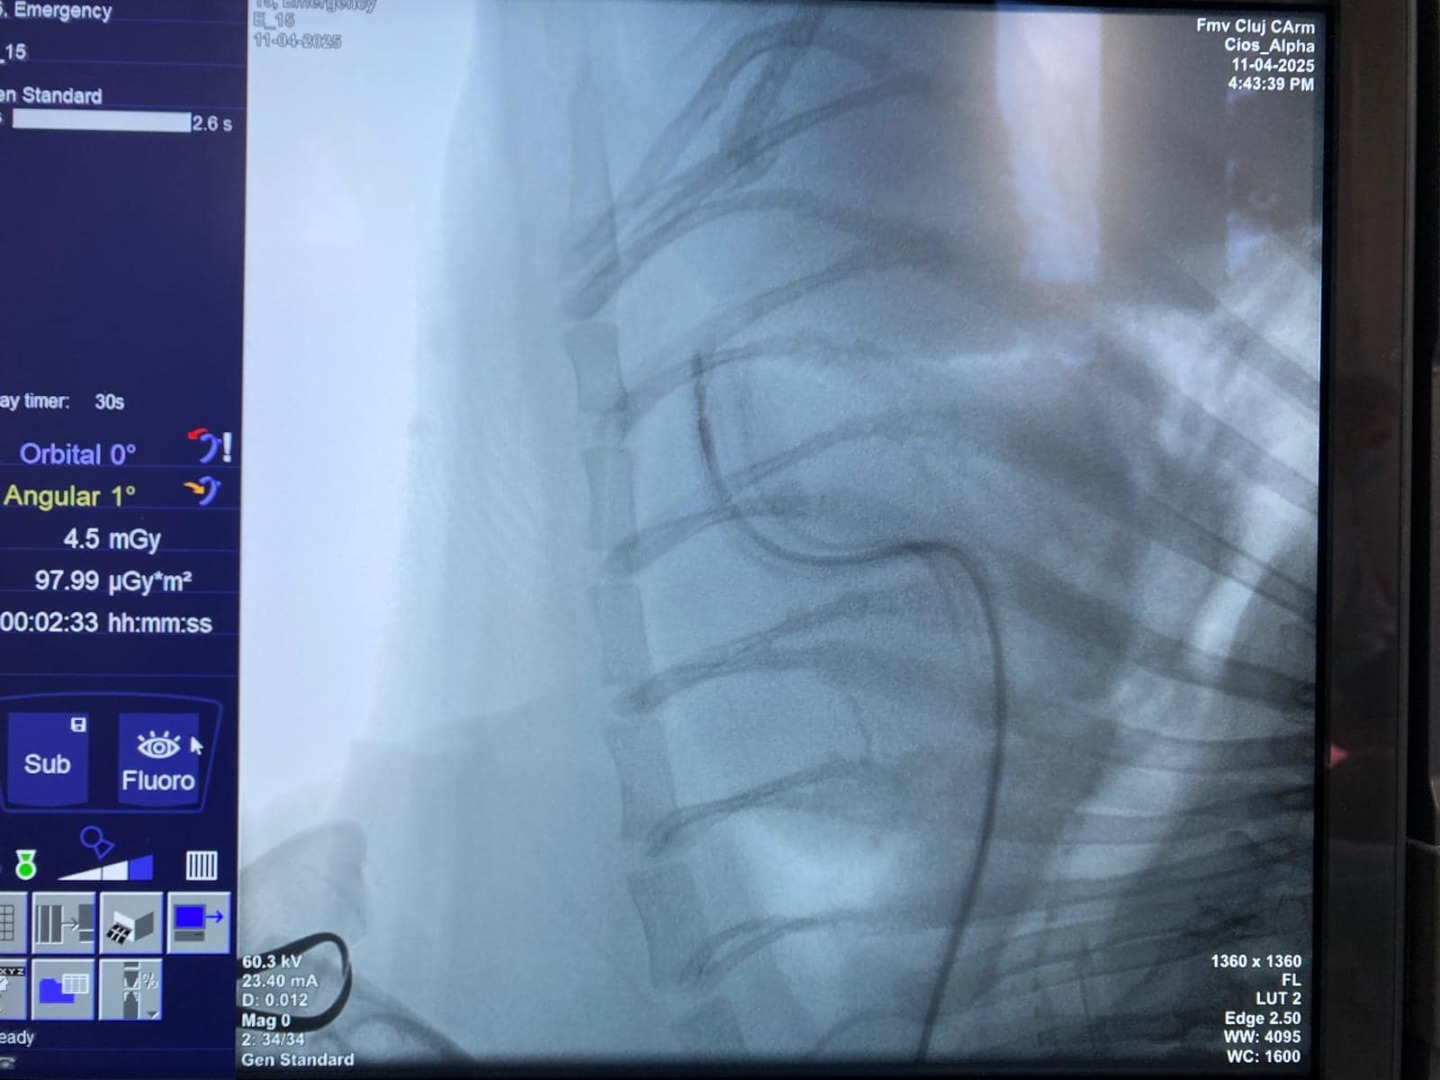

După câteva zile în care Arni a suferit mai multe episoade de sincopă – scurte pierderi de conștiență care i-au înspăimântat familia –, totul s-a transformat într-o cursă contra cronometru. Datorită medicului veterinar Prof. Dr. Iuliu Scurtu (USAMV Cluj), care a colaborat cu Prof. Dr. Horia Roșianu, șeful secției de cardiologie de la Institutul Inimii, și cu Dr. Iulia Melega, specialistă în anestezie veterinară, Arni a avut o șansă reală.

Pe 11 aprilie, la ora 15:00, bulldogul a intrat în operație.

Operația a fost un succes. Stimulatorul a fost implantat, iar în acea seară, Arni s-a întors acasă.